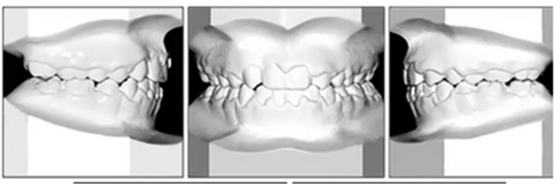

總體治療目標(biāo)已經(jīng)實(shí)現(xiàn)。病人的笑容和輪廓有所改善。咬合關(guān)系為I類磨牙關(guān)系,牙列整齊,牙尖交錯(cuò)關(guān)系良好。反合和中線偏移得以矯正,并實(shí)現(xiàn)了正常的覆蓋和覆合。上下牙弓的擁擠問題完全解決,并且完成后全景片顯示良好的牙根傾斜度。疊加顯示良好的縱向和垂直控制(ANB,3.5°; SN / GoMe,42.5°)和矯正上下頜前牙傾斜度(1 / SN,96°; IMPA,87°)(圖10 ; 表)。

經(jīng)過24個(gè)月的保持后,咬合保持得很好(圖11 ; 圖12)。在上牙弓中,應(yīng)用固定舌側(cè)保持器以防止任何復(fù)發(fā)傾向。在下牙弓中,治療后拔除第三磨牙。